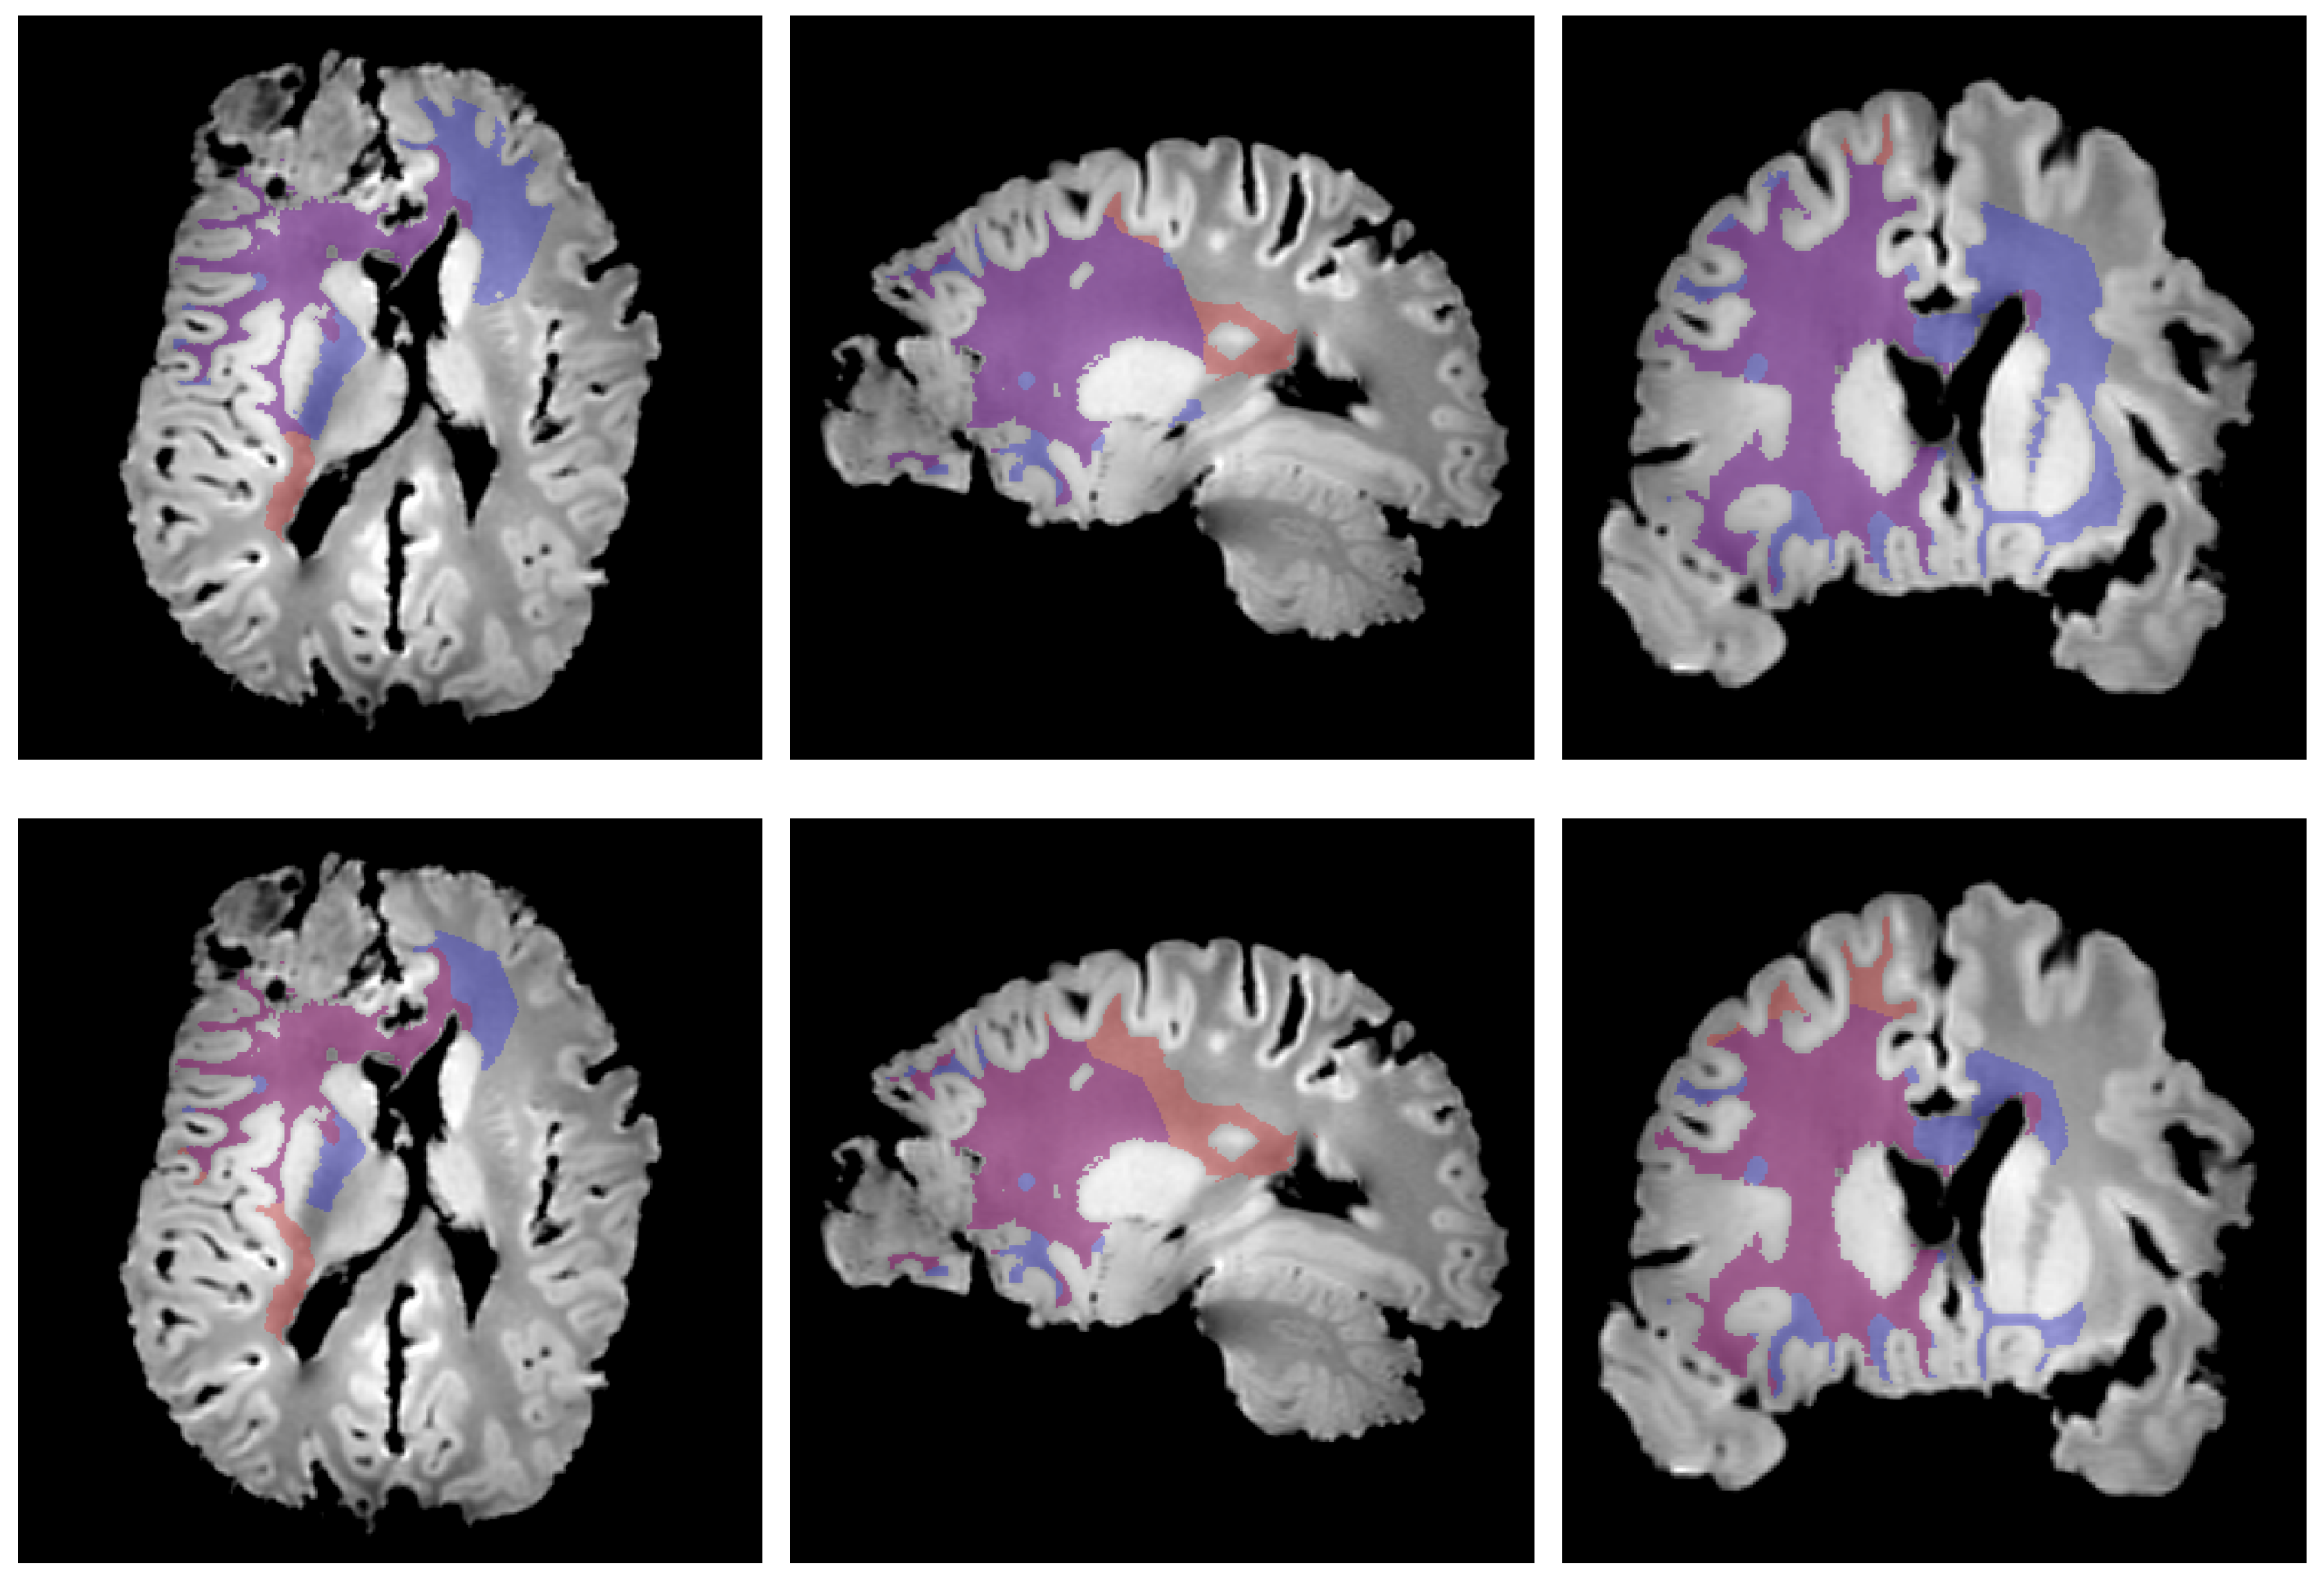

2.6. Cell Density Maps to Ex Vivo T1 Registration

2.7. Edema Delineation

3. Results